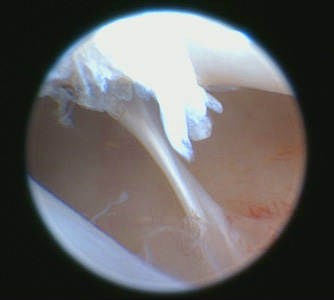

Artroscopia: perforazione retrodiscale Artroscopia: aderenza fibrosa

Artroscopia: taglio di un’aderenza Artroscopia: eliminazione dell’infiammazione con radiofrequenza